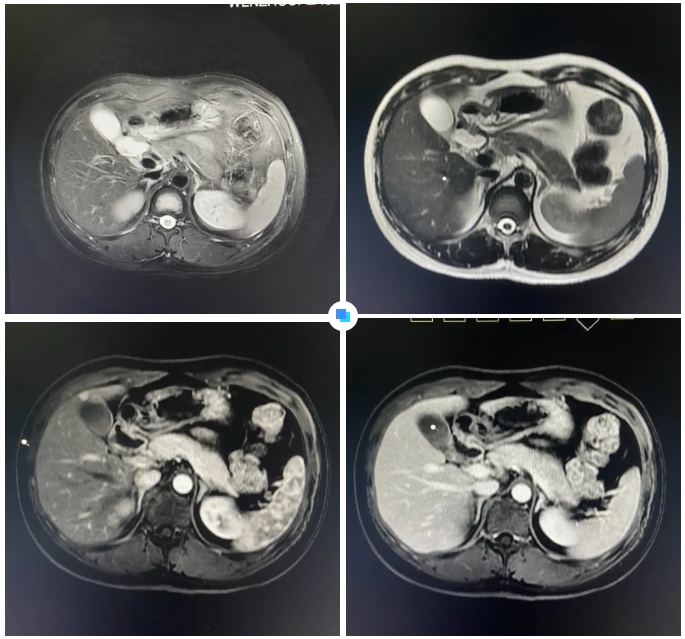

00后小伙查出7mm肝癌!多虧“神探”醫(yī)生精準(zhǔn)識(shí)別早癌信號(hào)

最近,和平國(guó)際醫(yī)院影像中心團(tuán)隊(duì)如同“神探般”揪出了隱藏在26歲小伙體內(nèi)7mm的微小肝癌。

其實(shí),診斷過(guò)程中還有一個(gè)小插曲:在和平國(guó)際醫(yī)院被初步查出疑似小肝癌病灶后,患者馬上前往上海大三甲醫(yī)院進(jìn)行再次檢查,結(jié)果并沒(méi)有發(fā)現(xiàn)病灶。

▲ 和平國(guó)際醫(yī)院影像診斷報(bào)告

但和平國(guó)際醫(yī)院的影像報(bào)告引起了三甲醫(yī)院專(zhuān)家的重視。通過(guò)將兩家醫(yī)院的影像資料進(jìn)行對(duì)比分析,最終找到了患者肝臟內(nèi)的7mm病灶。隨后的手術(shù)證實(shí),該病灶確實(shí)為微小肝癌。

因?yàn)椴≡铍x膽囊比較近,不具備射頻消融的條件,所以連著膽囊一起切掉。目前,患者恢復(fù)良好,其家屬感激之余,特地送來(lái)錦旗以表敬意。

在被問(wèn)到如何發(fā)現(xiàn)隱藏如此深的病灶時(shí),和平國(guó)際醫(yī)院影像中心執(zhí)行主任侯文杰講到,該病灶在平掃T1、T2項(xiàng)都非常不清楚,只有彌散加權(quán)的情況下,病灶區(qū)域顯示出輕微的高信號(hào),這一細(xì)微線(xiàn)索引起了他的高度關(guān)注。

隨后的增強(qiáng)核磁掃描發(fā)現(xiàn),在動(dòng)脈期病灶顯著強(qiáng)化,而在門(mén)脈期明顯減退,這一特征與微小肝癌的表現(xiàn)高度吻合。

“肝癌不可怕,早期發(fā)現(xiàn)是關(guān)鍵。”侯文杰主任講到,肝癌的五年生存率較低,但早期的小肝癌一旦發(fā)現(xiàn),預(yù)后效果會(huì)非常好。磁共振(MR)檢查可以發(fā)現(xiàn)亞厘米級(jí)肝癌、乃至癌前不典型增生結(jié)節(jié),為臨床醫(yī)生開(kāi)展腫瘤早期手術(shù)切除術(shù)或介入等相關(guān)外科治療方案提供了精準(zhǔn)的影像依據(jù)。